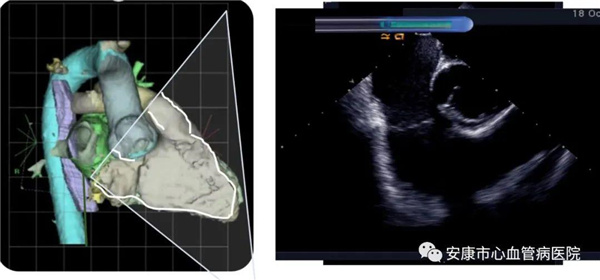

心律失常团队在11月6日为患者在ICE引导下行房扑射频消融术。穿刺左锁骨下静脉,导丝走行证实了合并永存左上腔静脉。穿刺右股静脉,分别送入心腔内超声导管和消融电极,超声下建立右心室、右心房、左心室、左心房、二尖瓣和三尖瓣及三尖瓣峡部模型。ICE就像术者多了一双天眼,可以对心脏内部结构一目了然,360度无死角观察心脏结构,可以做到“所视即所及”。建模后,消融三尖部峡部,房扑很快终止,转为窦性心律,手术获得成功!手术用时仅70分钟,术后病情稳定,安全返回病房。

心腔内超声(Intracardiac Echocaiography ICE)是将微型的换能器安装在心导管的尖端,再经外周血管(动脉或静脉)送至心腔,换能器发射声波,然后将接受到的回波经计算机处理后形成超声图像。由于换能器放置在心腔内,不受空气等因素的干扰,因此比经食道超声检查图像更加清晰,可以辨别心内的细微结构,临床上主要用于指导心律失常的射频消融治疗。

ICE不仅能检查左心耳结构、指导房间隔穿刺,而且能精确构建左房及肺静脉解剖结构,量化前庭部位与肺静脉口部的距离,精准的消融一些复杂心律失常病例;并且能精确构建食道,量化食道与后壁的距离,降低食道损伤几率;术中动态监测积液变化,实时监测并发症,早发现早处理。因此心腔内超声真可谓是房颤射频消融手术安全保障的一只“天眼”。此外这只“天眼”现在还应用于心脏瓣膜手术、起搏器植入等心脏介入手术。